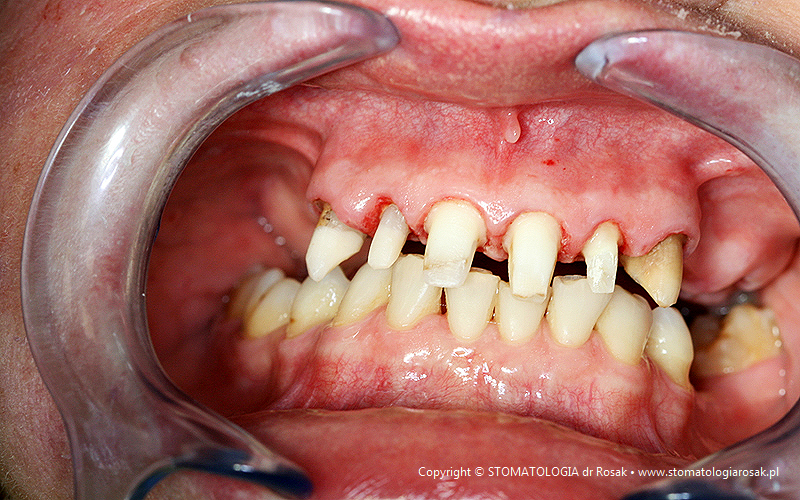

9. Pacjent lat 57- zgłosił się celem usunięcia zniszczonych zębów i wykonania protez ruchomych całkowitych.

NIE USUNĘLIŚMY - ANI JEDNEGO ZĘBA!!!

| 9a. Przed leczeniem |

9b. Gotowe korony i mosty porcelanowe na górze

(trójkę górną prawą pacjent zażyczył sobie nie korygować)

oraz w żuchwie tzw. czapeczki pokrywające oraz zatrzaski kulowe dla lepszego utrzymania protezy ruchomej dolnej |